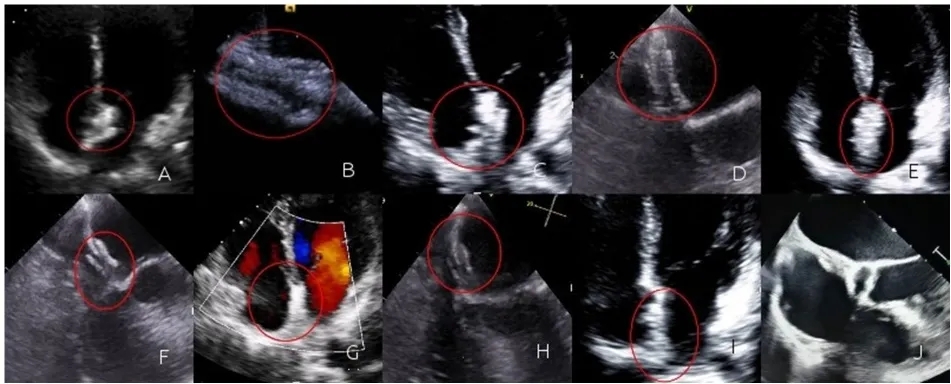

在1个月的随访期间,生物可降解封堵器组的52名患者复查了经胸右心声学造影(cTTE)。其中8名患者有I级分流,4名患者有II级分流,其余患者未见明显分流。金属封堵器组的70名患者复查了cTTE。其中13名患者有I级分流,8名患者有II级分流,其余患者未见明显分流。两组的残余分流率相似(生物可降解封堵器组对比金属封堵器组:7.7%对比11.4%;p=0.493)。在6个月的随访期间,生物可降解封堵器组的45名患者复查了cTTE。其中8名患者有I级分流,3名患者有II级分流,其余患者未见明显分流。金属封堵器组的63名患者复查了cTTE。其中10名患者有I级分流,7名患者有II级分流,其余患者未见明显分流。两组的残余分流率相似(生物可降解封堵器组对比金属封堵器组:6.7%对比11.1%;p=0.432)。在1年的随访期间,生物可降解封堵器组的38名患者复查了cTTE。其中,7例患者出现Ⅰ级分流,1例患者出现Ⅱ级分流,其余患者未见明显分流。在金属封堵器组中,51例患者复查了经胸超声心动图。其中,8例患者出现Ⅰ级分流,4例患者出现Ⅱ级分流,其余患者未见明显分流(图2)。两组的残余分流率相似(生物可降解封堵器组对比金属封堵器组:3.6%对比7.8%;p=0.291)。

图2.(A)术后即刻TTE显示封堵器三明治结构;封堵器清晰可见,并与房间隔同步运动;(B)术后即刻TEE可见左盘呈圆形轮廓;(C)术后1个月,TTE显示封堵器三明治结构;封堵器清晰可见,并与房间隔同步运动;(D)术后1个月,TEE可见左盘呈圆形轮廓;(E)术后3个月,TTE显示封堵器三明治结构;封堵器清晰可见,并与房间隔同步运动;(F)术后3个月,TEE可见左盘呈圆形轮廓;(G)术后6个月,TTE显示封堵器清晰可见,封堵器轮廓模糊,三明治结构逐渐模糊,且与房间隔同步运动;(H)术后6个月,TEE可见左盘呈圆形轮廓,封堵器逐渐降解;(I)术后1年,TTE图像不够清晰,封堵器三层结构消失;(J)术后1年,TEE显示封堵器处有再生组织,再生组织与房间隔隐约形成三层间隔。